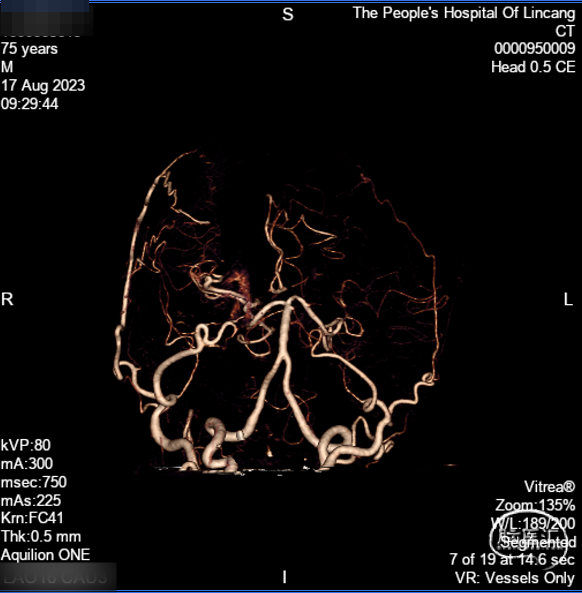

术前CTA:双侧颈内动脉闭塞,代偿可。

右侧颈总正侧位:见右侧颈内动脉闭塞,颅外血管代偿良好。

左椎正侧位:椎基底动脉未见异常,可见部分代偿。

左颈总正侧位:左侧颈内动脉闭塞,可见血管残端。